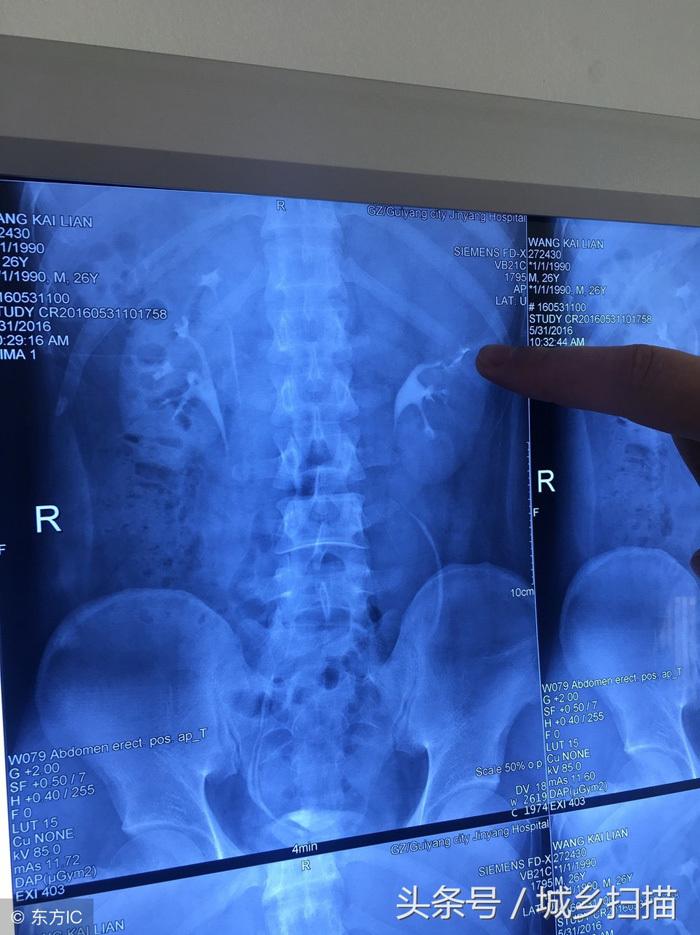

Vương Khai Luyện một lần bị đau dữ dội ở phần lưng eo, vì không chịu nổi mới đến bệnh viện kiểm tra. Sau khi kiểm tra, chụp X quang các bác sĩ phát hiện anh Vương có 4 quả thận. Bác sĩ cho biết, thận trên bên trái của anh bị ứ nước nghiêm trọng, bao phủ và chèn ép thận dưới bên trái, kèm theo nhiễm trùng gây ra một loạt các triệu chứng như đau lưng eo và sốt.

Kết quả chụp X-quang khiến bác sĩ phải bất ngờ

Vương Khai Luyện có 4 quả thận, mỗi bên 2 quả, mỗi bên có hệ thống cung cấp máu và hệ thống bài tiểu. Hai quả thận ở mỗi bên dài như một em bé dính liền. Thận của một người bình thường có kích thước tương đương với nắm tay của người đó. Bốn quả thận của Vương Khai Luyện nhỏ hơn người bình thường và chỉ bằng cỡ nắm tay của em bé.